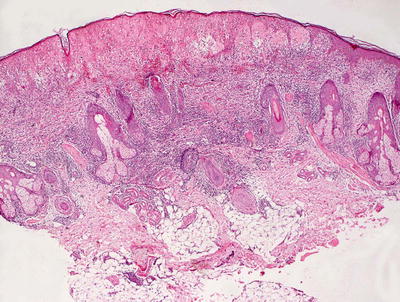

3.8.2 Histology

The histologic findings in hydroa vacciniforme are not specific. The epidermis is markedly spongiotic in early lesions, progressing to reticular degeneration and ultimately necrosis in later stage lesions (Fig. 3.17). Within the dermis, there is a brisk infiltrate that consists predominantly of lymphocytes and histiocytes (Figs. 3.18 and 3.19). Eosinophils are not abundant. Neutrophils may be observed in ulcerated lesions, but this is likely a secondary phenomenon.

Fig. 3.17

Hydroa vacciniforme demonstrates a subepidermal blister with abundant dermal edema and a brisk inflammatory infiltrate

Fig. 3.18

A brisk inflammatory infiltrate in the dermis extends into the overlying epidermis in hydroa vacciniforme. Blister formation is due to spongiosis and can be at any level

Fig. 3.19

Hydroa vacciniforme is characterized by a brisk superficial and often deep dermal inflammatory infiltrate